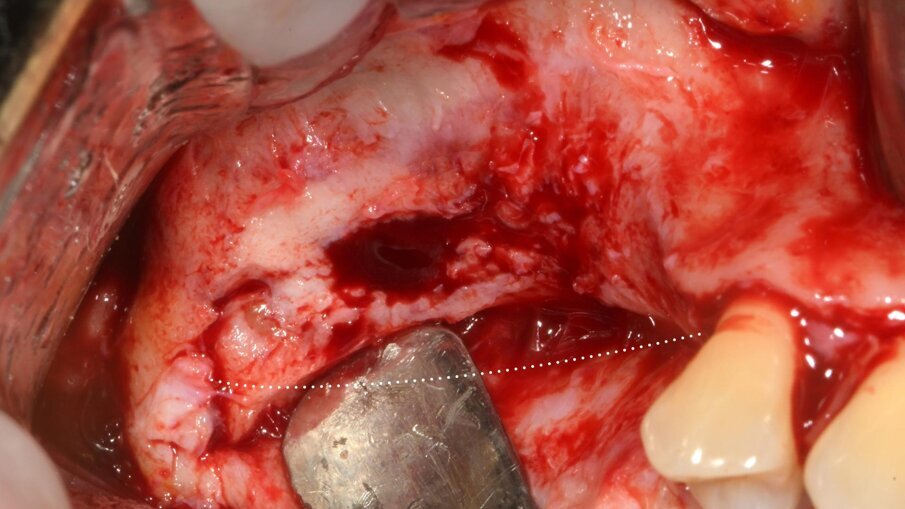

Dopo 9 mesi, è stata eseguita una seconda CBCT per valutare il volume di osso rigenerato e per pianificare la chirugia computer guidata (Fig. 23); i file .STL ottenuti dalla scansione 3D e i files .DICOM della CBCT sono stati utilizzati per pianificare l’inserimento degli impianti tramite una chirurgia computer guidata (Navimax, Biomax) (Fig. 24) . Il giorno della chirurgia implantare (T1), è stata eseguita un’incisione orizzontale para-crestale, per permettere l’esposizione della griglia e la sua rimozione, previa rimozione delle viti in titanio e dell’osso formatosi al di sopra di essa (Figg. 25, 26). L’esame clinico ha evidenziato una completa rigenerazione ossea del difetto osseo verticale, con assenza di pseudo-periostio o pseudo-periostio minore di 1 mm, di conseguenza pseudo-periostio di “classe 1” secondo la classificazione di Cucchi et al.20 (Figg. 27, 28). Successivamente, la dima chirurgica è stata posizionata e fissata nella posizione pianificata; i siti implantari sono stati preparati con frese progressive dedicate; e tre impianti conici (T3, Zimvie) sono stati inseriti nelle posizioni #15, #16 e #17, secondo la pianificazione protesicamente guidata eseguita precedentemente mediante il software da chirurgia guidata (Figg. 29-31). Gli impianti sono stati “sommersi”, attendendo la corretta osteointegrazione, ed è stata eseguita una chiusura per prima intenzione (Fig. 32). Dopo il posizionamento degli impianti, è stata eseguita una radiografia OPT (Fig. 33).